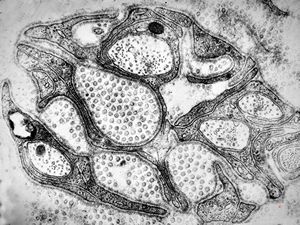

M,3y. | globoid leukodystrophy of Krabbe - n.suralis